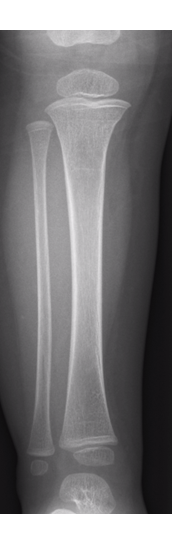

Proximal tibial buckle fracture